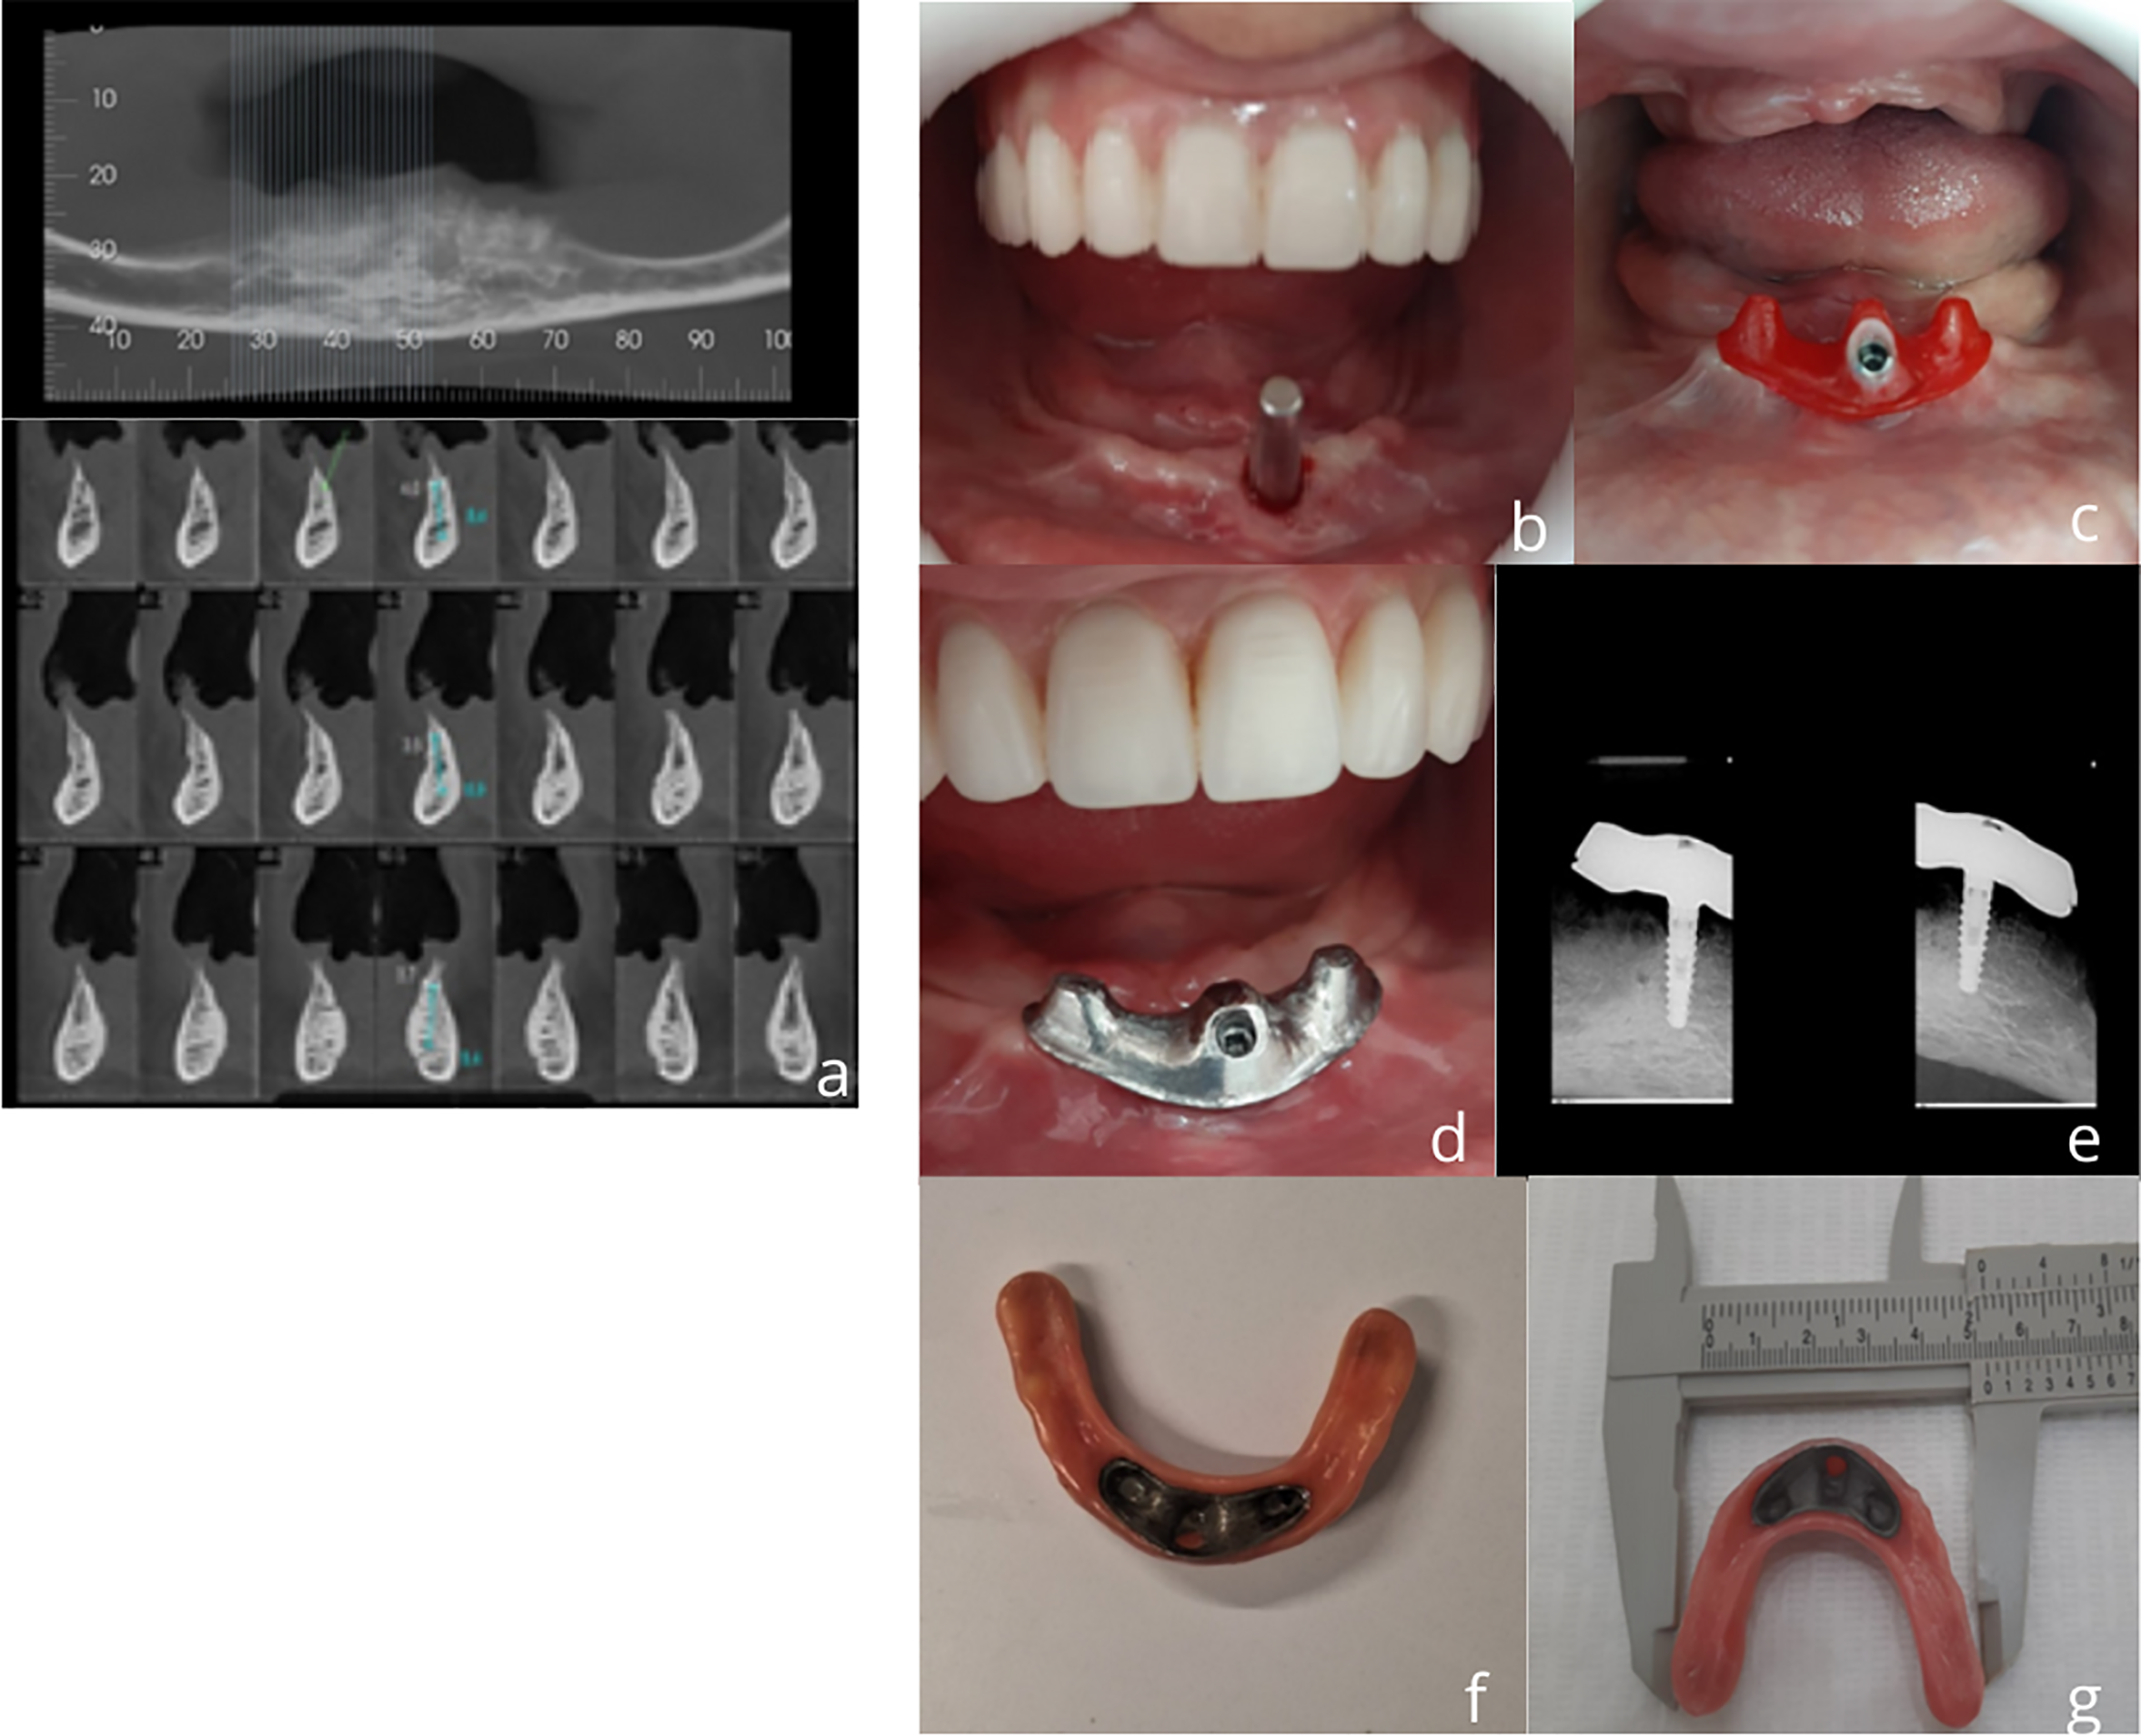

After a 4-month osseointegration period, the implant was activated. A careful transfer impression of the implant and both arches was made using addition-cured silicone (Futura, DFL Ltda, Rio de Janeiro, Brazil). Stone casts were fabricated, and the T-OVER abutment was modeled in acrylic using a burn-out UCLA-type abutment for a 3.5 mm internal hex connection(Implacil, São Paulo, Brazil), and then cast in a cobalt-chromium alloy (Fig. 2).

Fig. 2. Clinical study: baseline (2019)–a) Initial CBCT scan; b) buccal inclination of the implant (3.5/10 mm;internal hexagon); c) T-OVER abutment in acrylic modeling ; d) periapical radiograph with T-OVER installed; e) T-OVER cast in cobalt-chromium; f) basal view of the prosthesis; (g) overdenture base adaptation area measuring 45 mm.

A set of complete dentures was fabricated, with proper border and occlusal adjustments. The mandibular denture was adapted to the T-OVER abutment using a retentive slot for the pressure-fit retention system.

After four weeks of functional loading (T1), clinical follow-up visits were performed quarterly during the first year and biannually thereafter. Clinical assessments included the modified plaque index, peri-implant bleeding on probing (BOPi), peri-implant probing depth (PPDi), and keratinized mucosa height. Radiographic evaluation involved measuring the marginal bone levels from the implant platform to the alveolar bone crest (Fig. 2). The final follow-up (T2) was performed in 2024, representing a 5-year follow-up period (Fig. 3).